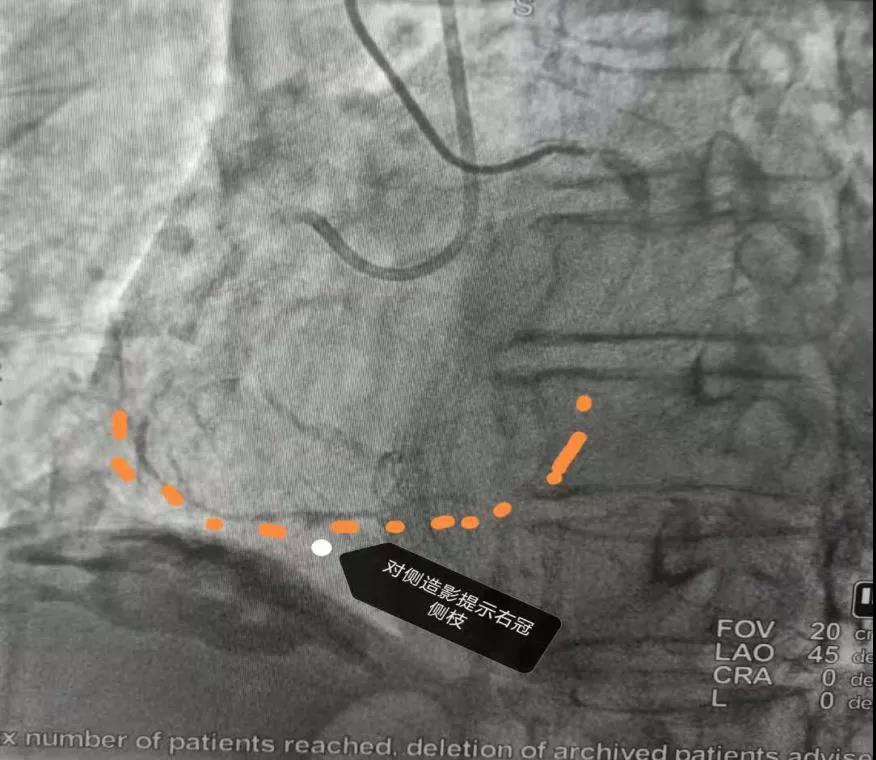

对侧造影能看到右冠状动脉闭塞段以远了

2.jpg

3.jpg